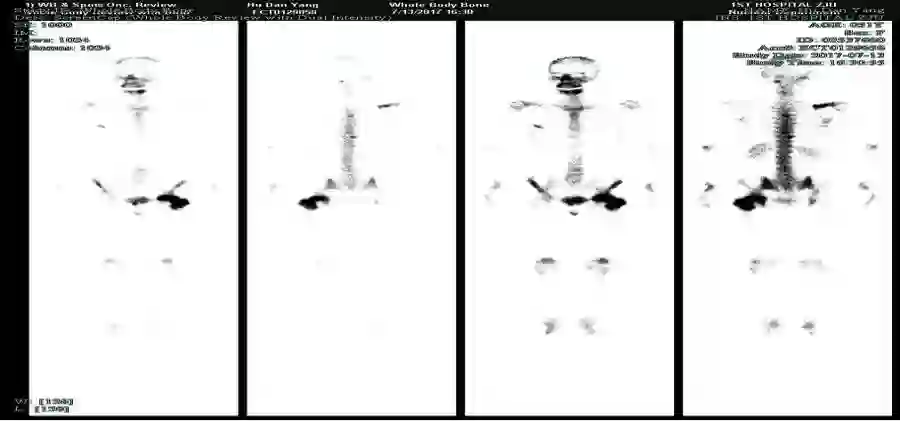

图三:2017.3.13骨骼ECT提示:颈椎上段左缘、右侧肩胛骨、右侧1后肋及5前肋、胸5、10椎体、双侧耻骨及左侧股骨上段见示踪剂分布异常浓聚。

于是我院再次组织MDT讨论,选择戈舍瑞林+氟维司群作为内分泌维持治疗方案(经检查确认胡女士尚未绝经),并继续给予唑来膦酸。患者耐受性良好。2017年7月骨骼ECT复查提示部分骨病灶代谢较前有所降低。